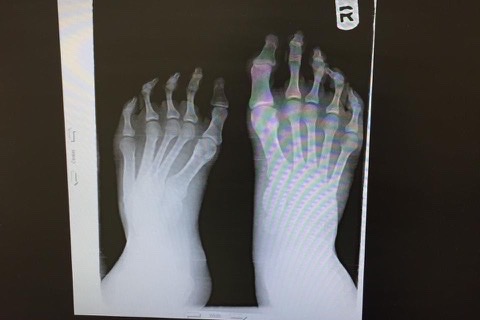

As many of you know, my brother Dj aka Derek has been battling with club foot since he was born. With unsuccessful reconstructive surgeries as a baby, his leg began to develop differently than the other. The pain and issues he had as a child stopped him from his love of playing football. He had to always buy shoes that fit one foot, but was 3 sizes too big for his club foot. After years of various braces, supports, stockings and on going struggles, he kept on going.

In 2014 he had his first complete reconstructive surgery. For months he wore an external fixator which every day needed to be turned to slowly reconstruct the bones in his foot, toes & ankle. He worked with his Dr for two years between physical therapy, readjustments, more braces, casts and special shoes. This surgery not only caused my brother to have a permanent limp, but now was in CONSTANT pain. He went from running, walking long periods of time and being a normal young 20 year old guy to one who cannot run, and walks with a struggle.

After this surgery and years of struggle... he was now worse off than before. This never stopped him.. he kept on working, he kept on fighting and he never let it get in the way of his happiness. After some time, Dj came in contact with a special team of Dr’s in NYC. Hoping to keep his foot, he went to this team and after months and months of appointments, pictures, preparation and OUT OF POCKET EXPENSES, he was ready for his SECOND reconstructive surgery! Although this one corrected a lot of the wrong doings from before, it never fixed the issue of pain and limping he now suffered from.